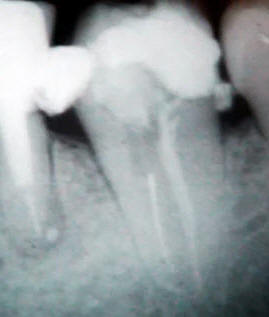

Secuencia técnica para eliminar instrumentos rotos en el conducto radicular

•  Una radiografía periapical preoperatoria y

•  una excelente visión del cabo fracturado  por medio del microscopio dental.

Con una punta de utrasonido para endodoncia se realiza una guía alrededor del instrumento fracturado, usando alternativamente lavajes de Hipoclorito, solución salina y EDTA

Con punta de ultrasonido se elimina el cabo fracturado.